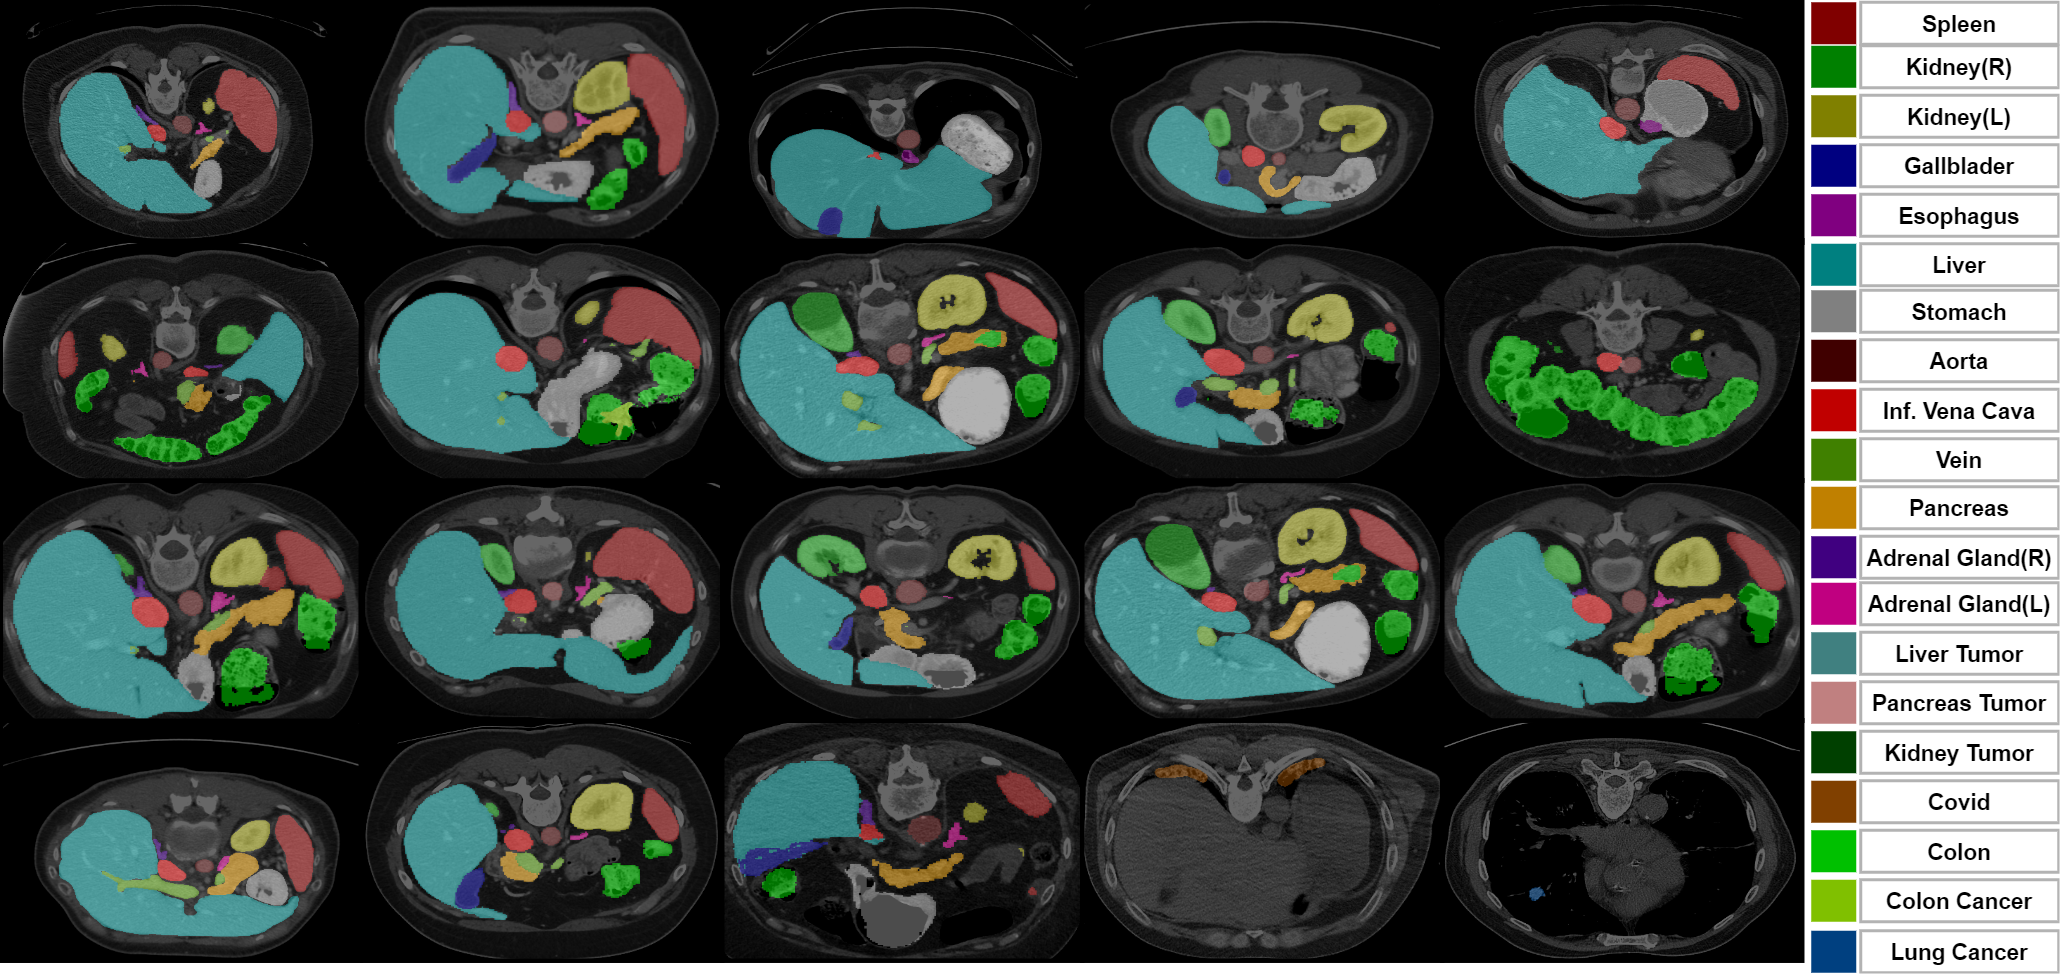

Fig. 2 VoComni dataset: 20K volumes with 20 organ & tumor classes of labels.